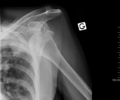

MRI of shoulder after dislocation with Hill-Sachs lesion and labral Bankart's lesion.

A systematic review of published literature concerning dislocation of the shoulder has indicated that young adults engaged in highly demanding sports or job activities should be considered for operative intervention to achieve optimal outcome.[24] Arthroscopic surgery techniques may be used to repair the glenoidal labrum, capsular ligaments, biceps long head anchor or SLAP lesion and/or to tighten the shoulder capsule.[25]